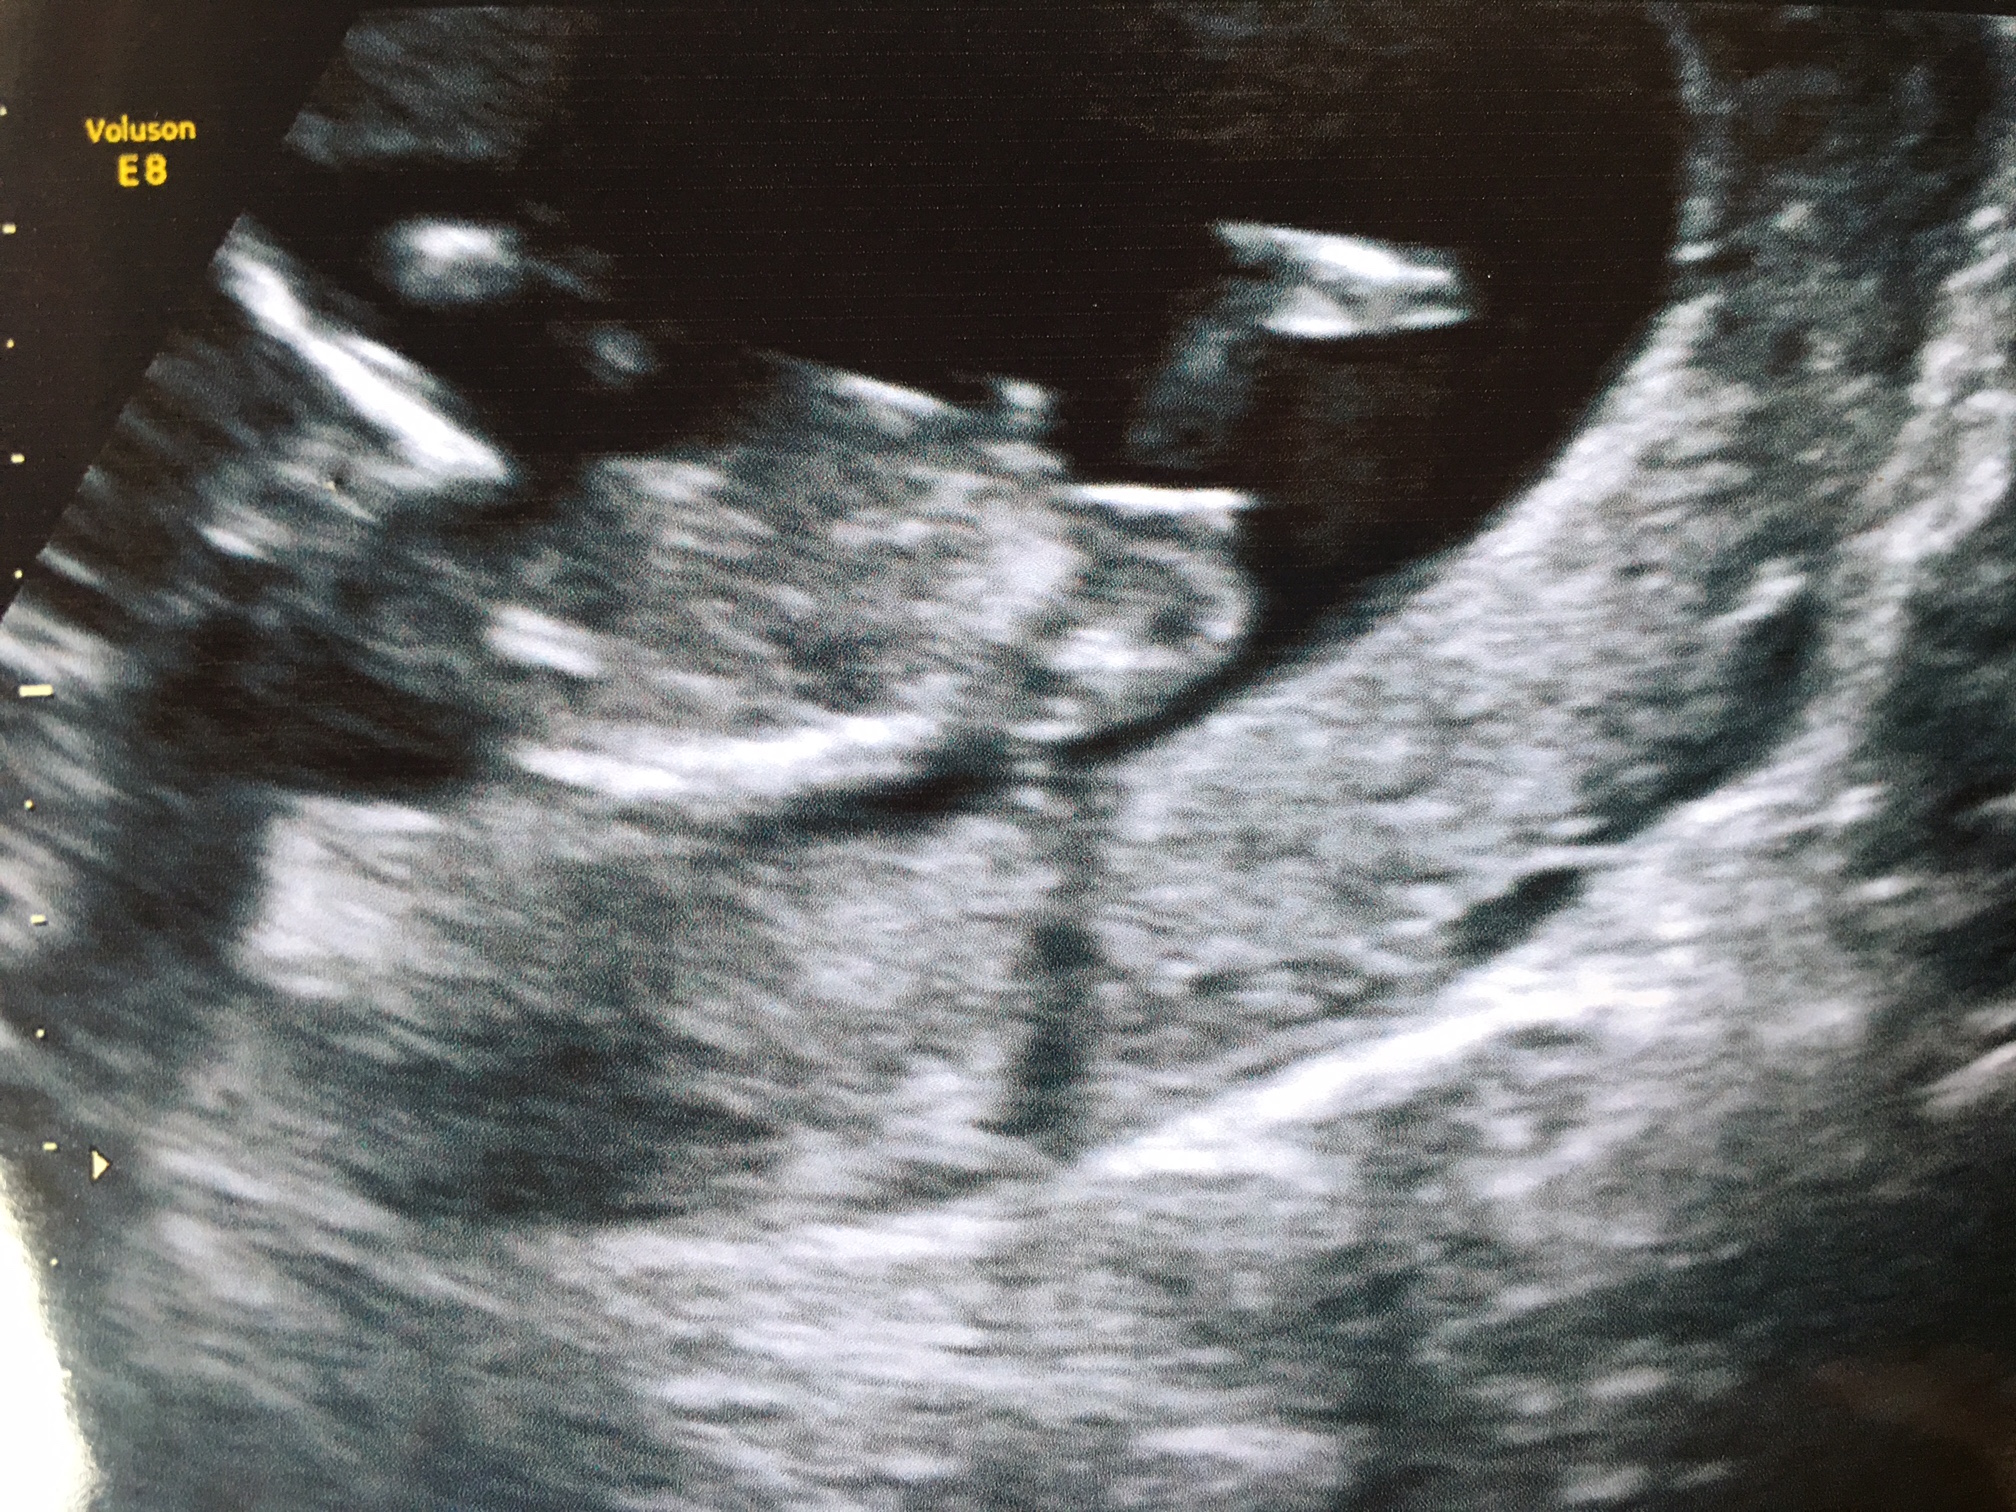

I know that these are not great quality but I'm hoping some of you may be more familiar with the nub theory than me and may know what my scan pictures might indicate - boy or girl?! I thought I was 12 weeks exactly, but they said I was measuring 12 + 3. Any guesses much appreciated!!